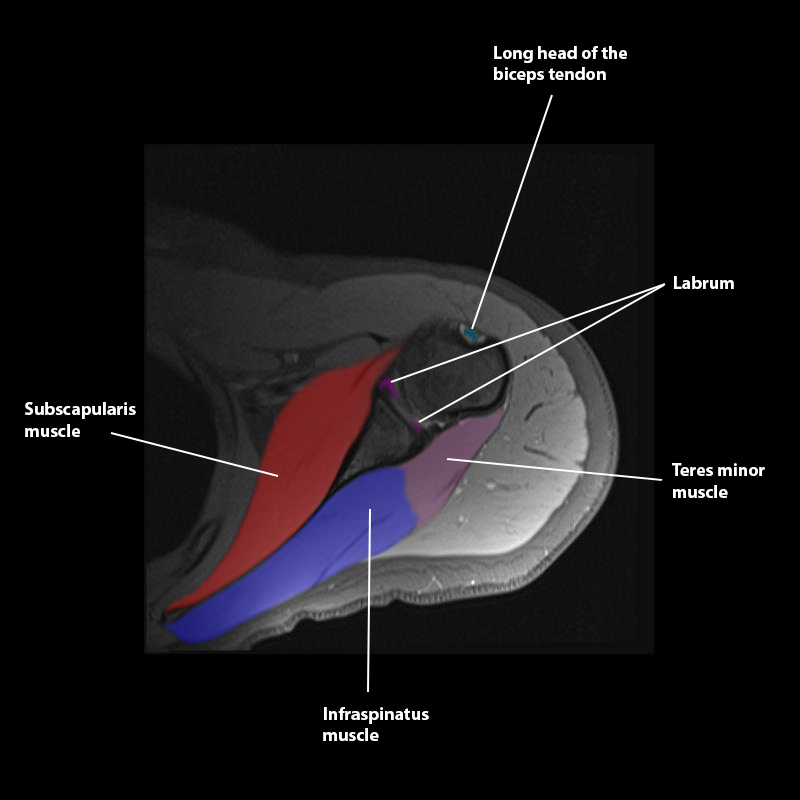

Shoulder MRI Anatomy